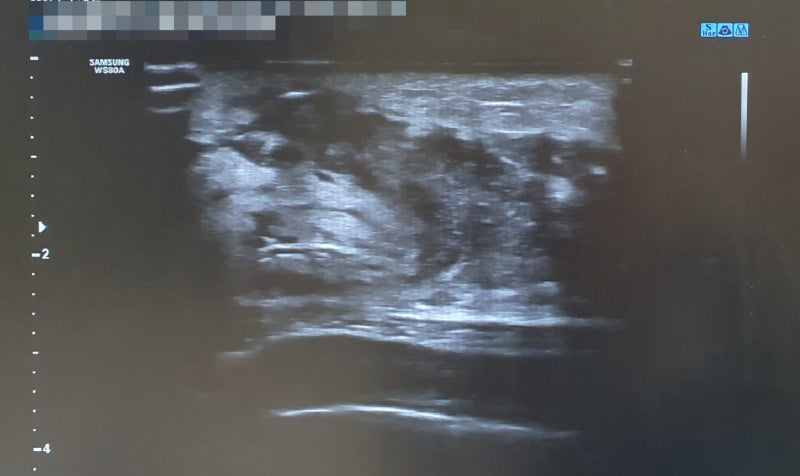

유방에서 응어리가 만져지거나 유두에서 피가 섞인 분비물이 비치는 경우, 피부함몰 등 유방질환을 의심하는 이상증상이 있는 경우 신속하게 의료기관을 방문하여 유방초음파검사를 받아야 합니다. 35세 이상의 여성이라면 2년에 한 번 정기적으로 유방 초음파 검사를 받는 것이 좋고, 40세 이상이면 1년에 한 번 정기적인 유방 초음파 검사를 추천합니다. 만약 고위험군에 해당하는 경우라면 의료진과 상의하여 보다 짧은 주기로 유방 초음파 검사를 받는 것이 필요합니다. * 유방질환 고위험군 – 모친이나 자매 중 유방질환에 대한 가족력이 있는 경우 – 40세 이상 출산 및 수유 경험이 없는 경우 – 과거 유방양성종양 진단력이 있는 경우 – 폐경 후 호르몬 치료를 받고 있는 경우

또한 임신 중인 임산부나 수유를 하고 있는 수유부의 경우에도 전농동 여성의 봄부터라면 유방 초음파 검사를 받을 수 있습니다. X선을 사용하는 유방촬영술의 경우 방사선 노출로 인해 임신부, 수유부의 경우 유방검사에 제한이 따랐으나 여성 봄유방초음파검사는 초음파를 사용하는 검사방법으로 방사선 노출이 없고 임산부, 수유부도 검사 진행이 가능하며 여러 차례 반복검사도 가능합니다.